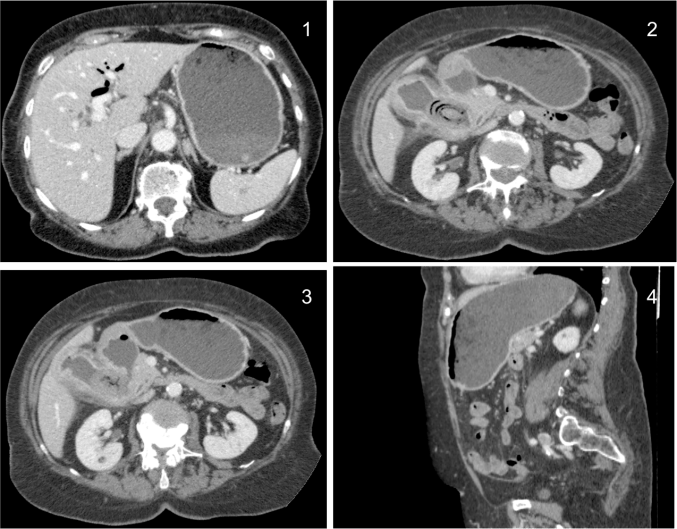

rx

Rx de Tórax 2P: llama la atención la cámara gástrica dilatada con abundante contenido con nivel hidroaéreo.

Se

Se observa un patrón en «miga de pan» que correlacionándolo con la radiografía corresponde con contenido en el interior del estómago dilatado.